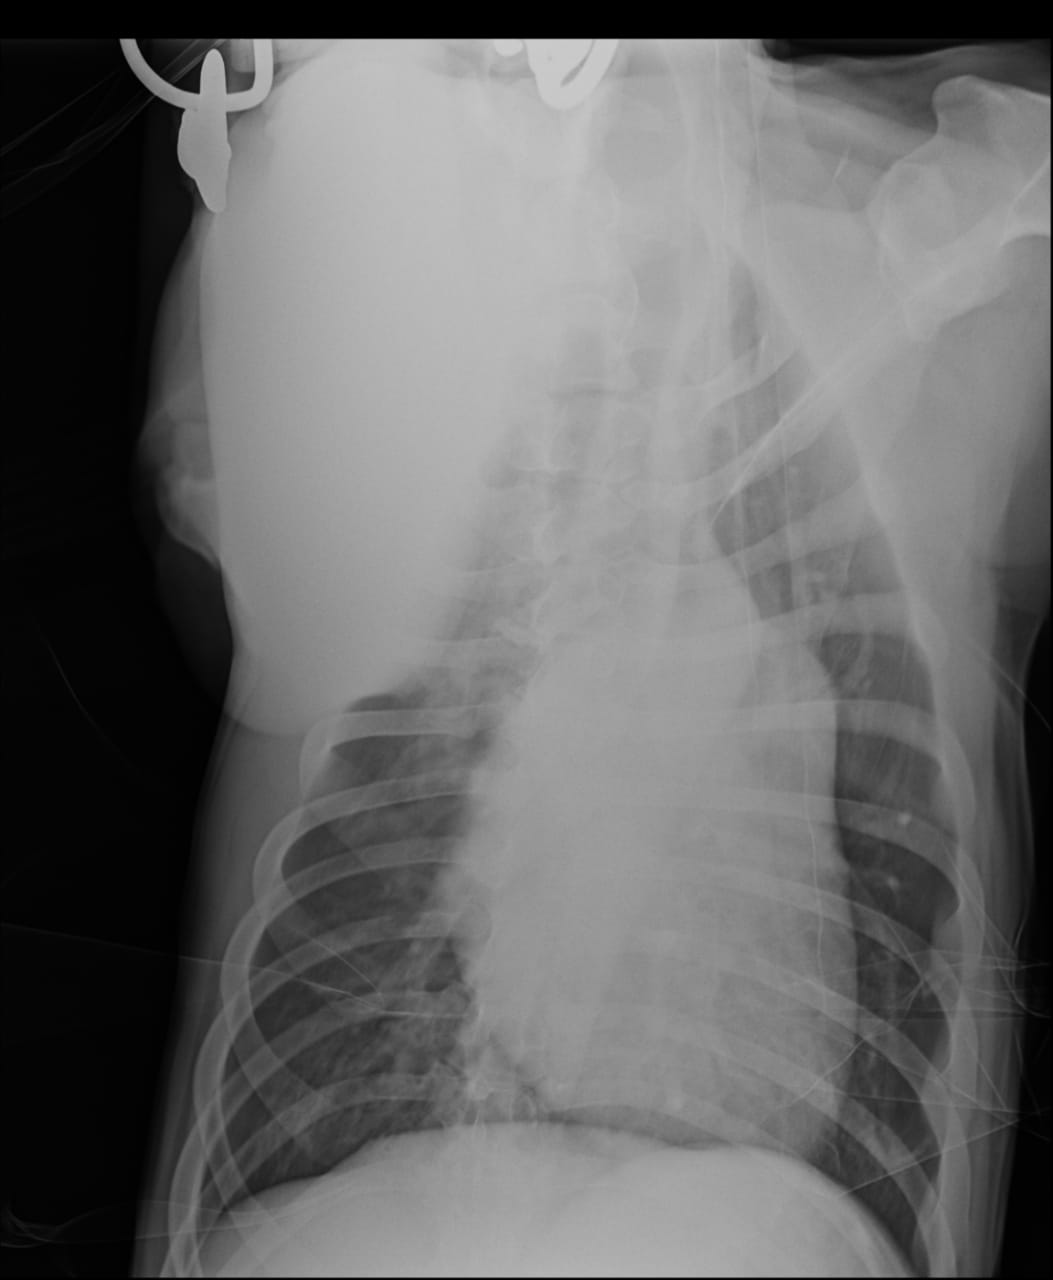

Анализы Арчи. Сердца и легких

Вложения

IMG-20220719-WA0100.jpg

IMG-20220719-WA0102.jpg

IMG-20220719-WA0104.jpg

IMG-20220719-WA0103.jpg

IMG-20220719-WA0105.jpg

Сегодня Арчуна Ирина возила на рентген легких и сдали анализ мочи. Результат анализа мочи готов будет завтра. Рентген легких выставляю.

Ирина, ждем твоего вердикта по рентгена и можно ли нам готовить Арчи к операции по глазам.

Антибиотика курс пропили.

Лучше чем было, но явно не норма:(